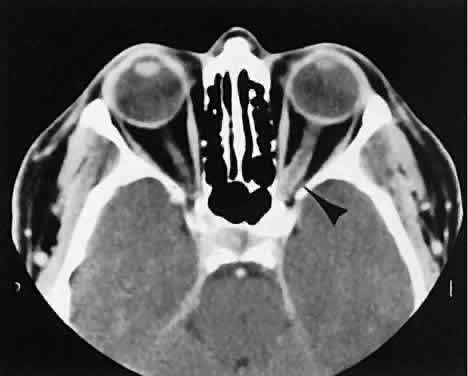

Graves' orbitopathy probably represents the most frequent cause of proptosis and EOM enlargement. The CT findings are fairly stereotyped and typically display various degrees of EOM enlargement (Fig. 7). The inferior rectus muscle usually is affected earliest, followed by the medial rectus, superior rectus, and finally the lateral rectus muscle. Rootman and colleagues13 noted more frequent involvement of the superior rectus/levator and medial rectus muscles than what had been reported previously with Graves' orbitopathy. These muscles can be affected in isolation, with the exception of the lateral rectus. To the best of our knowledge, isolated lateral rectus enlargement has not been reported in Graves' orbitopathy and in our experience usually is associated with a sphenoid wing meningioma.

Fig. 7. Graves' orbitopathy with two variations. Axial (A) and coronal (B) views show symmetric fusiform enlargement of the extraocular muscles with tapered muscle insertions. Note the predominant enlargement of the inferior, medial, and superior rectus muscles with lesser involvement of the lateral rectus muscle, a frequent pattern of enlargement in Graves' orbitopathy. Axial (C) and coronal (D) views of Graves' orbitopathy with expansion of retrobulbar ground substance and relative sparing of the extraocular muscles.

CT evidence of Graves' orbitopathy tends to be bilateral. Approximately 86% of patients with unilateral clinical findings have bilateral CT findings in our experience, which is consistent with the experience of others.42

Morphologically, the EOM belly is enlarged, with a gradual tapering toward and sparing of the tendinous portion of the muscle. Tendon involvement is a typical feature of orbital myositis. Tendon involvement helps to differentiate this lesion from Graves' orbitopathy, although Rootman and Nugent43 have noted a rare patient with Graves' orbitopathy with this finding.